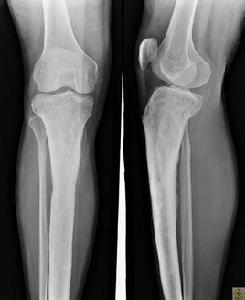

發病早期,經X線攝片顯示軟組織腫脹,10~14天后病骨出現不規則斑點狀脫鈣。以後隨病變發展,破壞與增生可同時存在,可見新生骨及死骨形成。

急性骨髓炎 x線表現⑴發病兩周內,為軟組織改變:肌間隙模糊或消失;皮下組織與肌間的分界模糊;皮下脂肪層內出現緻密紋影;軟組織充血、水腫,累及關節,可引起關節腫脹 ⑵發病兩周后,為骨改變:骨質破壞,嚴重破壞出現病理性骨折;不同形式的骨膜反應,骨包殼形成;死骨形成;一定程度的骨質增生。